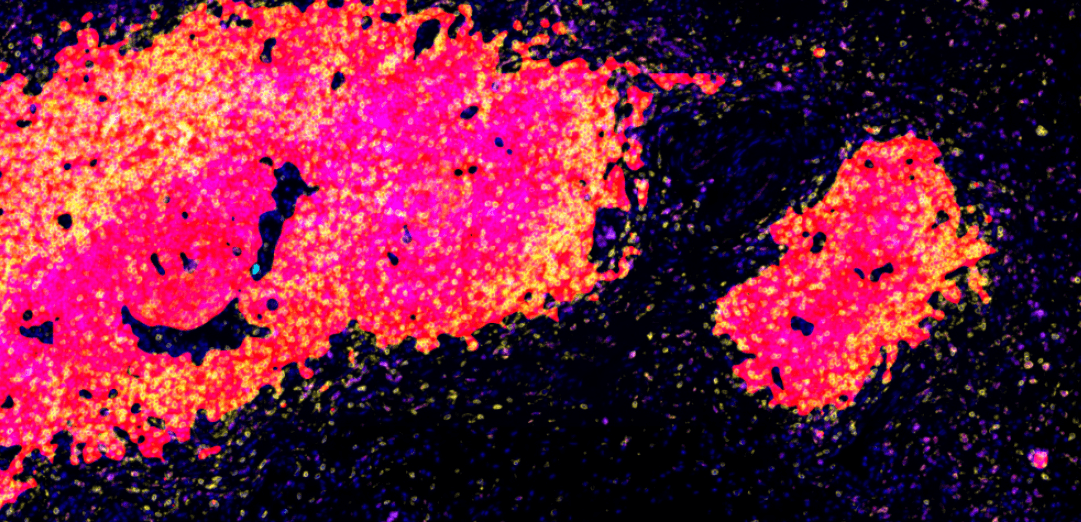

一次實驗檢測可標記 4~10個Marker,大幅提升檢測效率和資訊量

TSA 信號放大技術,提升微弱信號檢測靈敏度100倍以上

TSA (Tyramide Signal Amplification) 酪胺酸信號放大技術是多重免疫組織化學的金標準方法。我們的mIHC TSA Kits整合了最新的信號放大化學、抗體剝除技術和多色螢光標記系統,能在保持組織形態完整的前提下,實現10種標記的同時檢測,為腫瘤免疫微環境和細胞表型分析提供前所未有的技術支持。